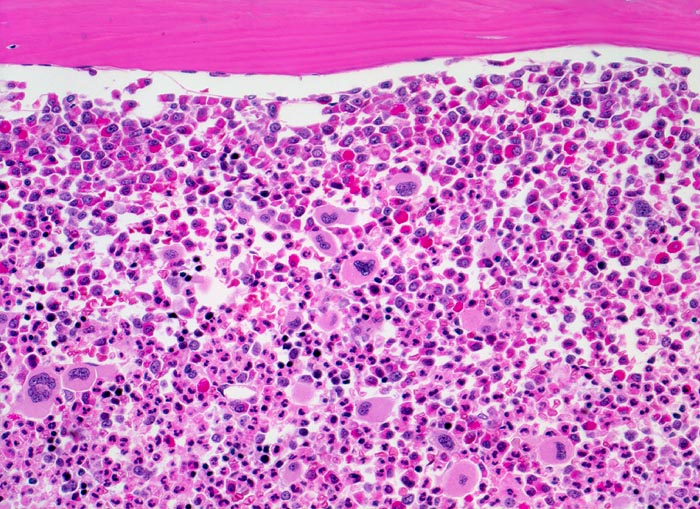

PathoPic – image database / PathoPic ID 3898 - chronische myeloische Leukämie (CML)

chronische myeloische Leukämie (CML)

Knochenmark, Beckenkamm

Extrem hyperzelluläres Knochenmark ohne Fettzellen. Hochgradig gesteigerte voll ausreifende neutrophile Granulopoese. Erkennbar sind verschiedene Reifungsstufen der Granulopoese, wobei die unreiferen Vorstufen (Myelozyten, Promyelozyten) bevorzugt entlang des Spongiosabälkchens paratrabekulär lokalisiert sind. Zur Mitte des Markraumes hin folgt die Reifungszone mit Prädominanz segmentkerniger Neutrophiler. Die normoblastäre Erythropoese ist fast vollständig verdrängt. Typisch ist die Vermehrung kleiner Megakaryozyten mit hypolobulierten Kernen.

Müdigkeit und Gewichtsverlust. Ausgeprägte Leukozytose, Basophilie und leichte Anämie. Palpable Milz.

Histologie

200